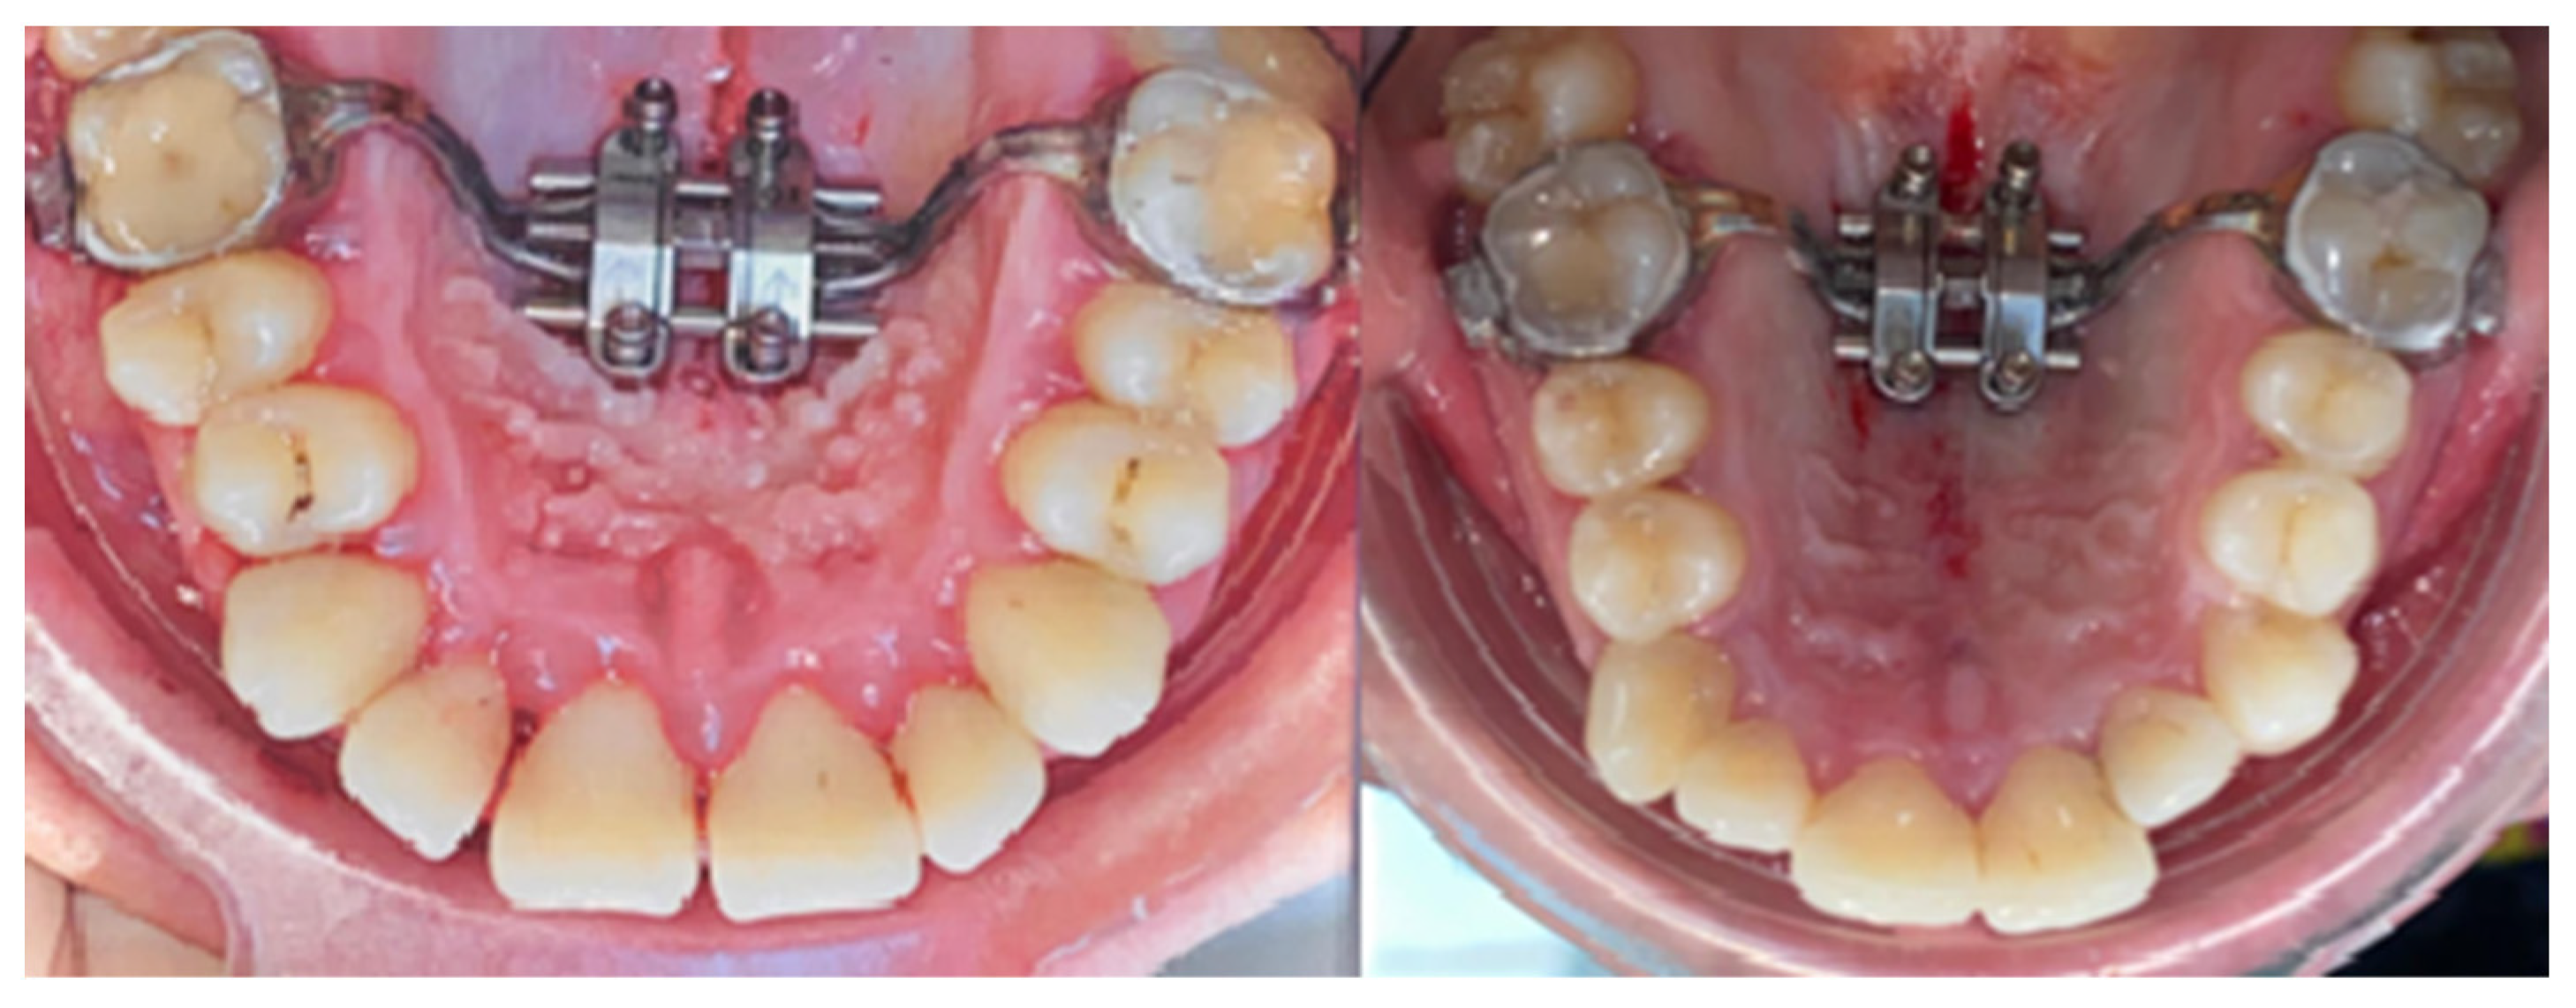

2.2. Palatal Expander Placement

2.3. Assessment of the Study Group